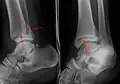

-

A triplane fracture of the ankle as seen on plain X-ray -